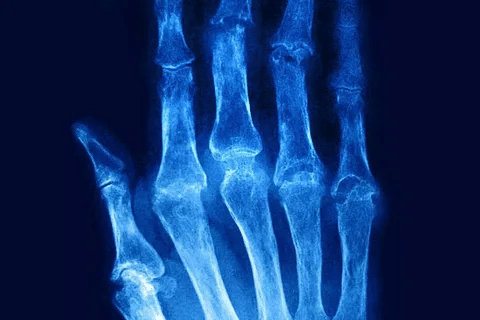

Research shows that RA causes widespread muscle pain, weakness, and deterioration. This affects up to 43 percent of patients.can rheumatoid arthritis cause muscle painArthritis In Fingers And Hands

Rheumatoid arthritis can cause muscle pain because it affects the whole body. RA is known for causing joint inflammation and pain. But it can also harm muscles and the body’s musculoskeletal system.

Many RA patients experience muscle pain and tenderness. Research shows that a lot of people with RA have muscle symptoms. This is because the muscles around inflamed joints get weaker over time.

Research has found a strong link between RA and muscle pain. Studies have looked into why RA causes muscle pain. They found that inflammatory cytokines and joint damage play a big role.